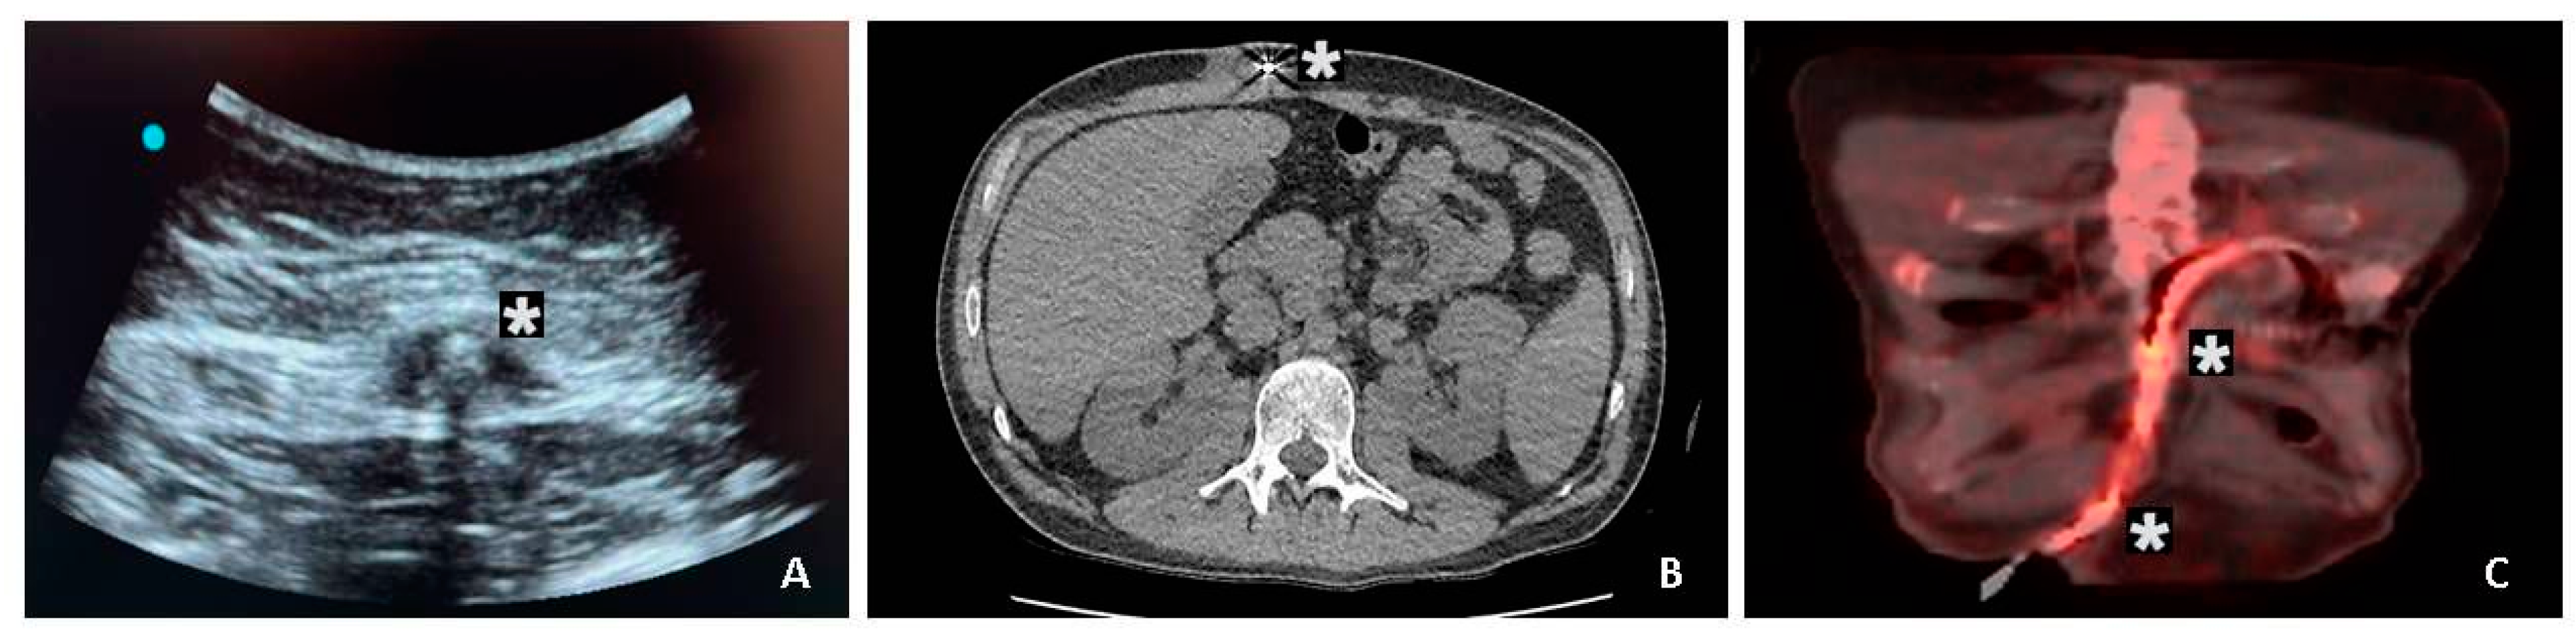

| Signs of infection by ultrasonography – no. (%) | 12 (60%) |